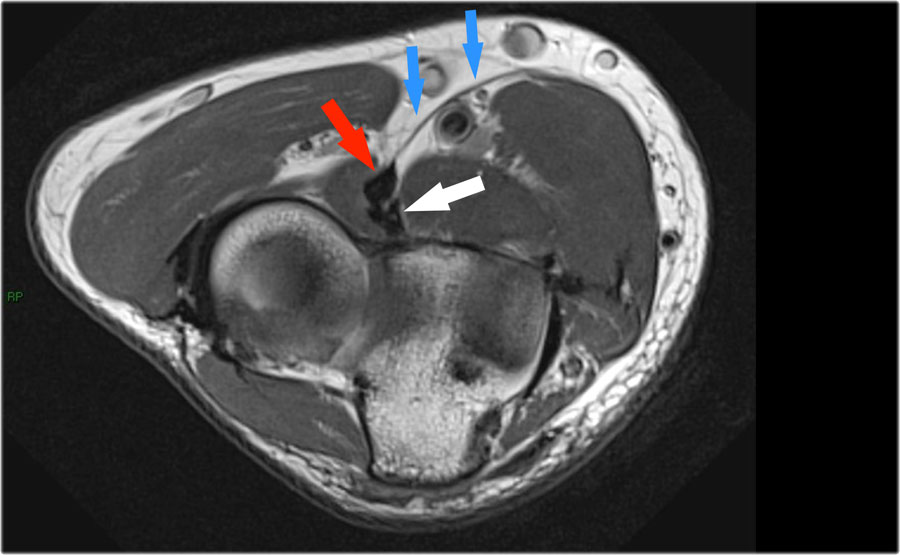

Khi quan sát trên lát cắt ngang (axial), chúng ta có thể nhận thấy sự hình thành gai xương khổng lồ.

Lưu ý rằng dây thần kinh trụ (mũi tên màu xanh) nằm cạnh các gai xương này và những bệnh nhân này có thể biểu hiện bệnh lý thần kinh trụ.